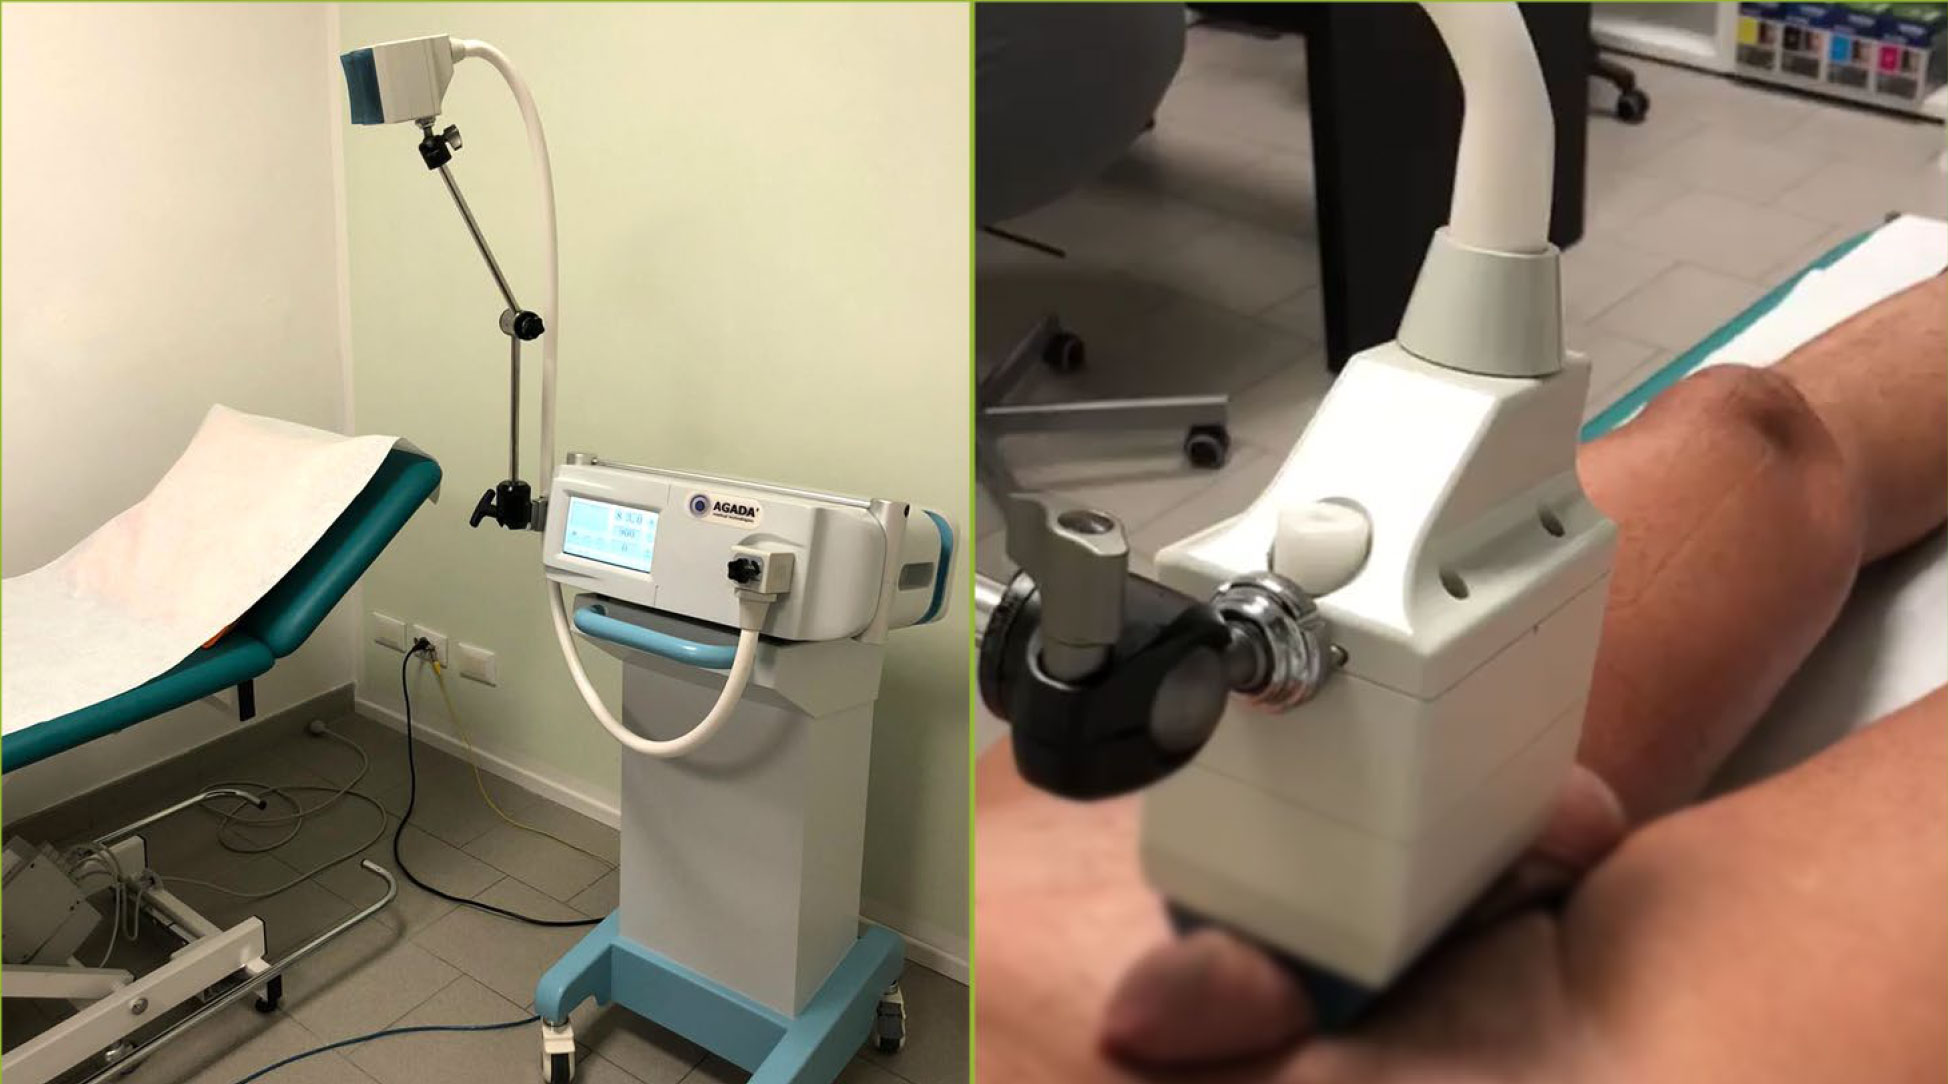

Magnetoterapia per SCIATALGIA Una Terapia che Funziona

Magnetoterapia per SCIATALGIA Una Terapia che Funziona.